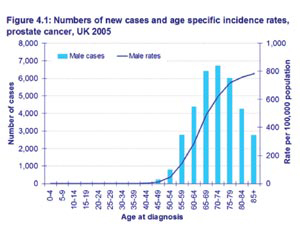

• η δακτυλική εξέταση (DRE – Digital Rectal Examination) και

• το διορθικό υπερηχογράφημα του προστάτη (TRUS – TRansrectal UltraSonography). Η επιβεβαίωση θα γίνει με τη βιοψία του προστάτη που γίνεται με ειδική βελόνα, κατά τη διάρκεια διορθικού υπερηχογραφήματος (για την επιλογή των ύποπτων περιοχών). Η βιοψία εκτός της επιβεβαίωσης της κακοήθειας θα δώσει και πληροφορίες για το βαθμό ατυπίας των κυττάρων (βάσει της δεκαβάθμιας κλίμακας Gleason) και κατά συνέπεια της επιθετικότητας του νεοπλάσματος.